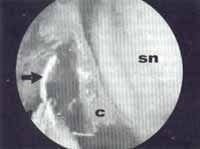

Otro método de impedir la lateralización o el colapso de un cornete medio inestable a la pared lateral nasal, es fijarlo endoscópicamente con sutura al septum nasal (Figura 5).

Figura 5. Cornete medio inestable, suturado endoscópicamente al septum nasal.

c = cornete medio. sn = septum nasal. pl = pared nasal lateral.

Flecha = aguja curva de sutura.